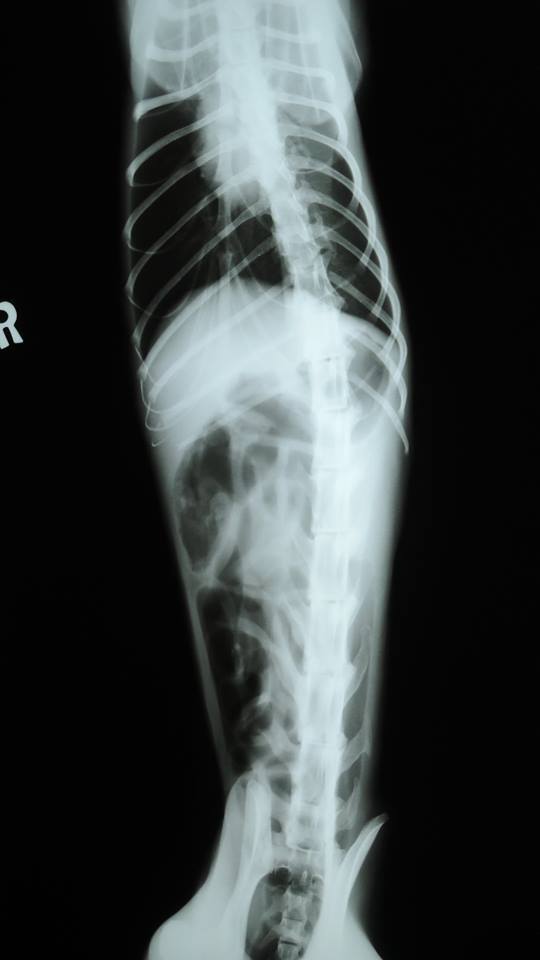

主題: 中和收容所感冒嚴重的橘貓 申請者姓名: 劉蕊瑄 花色: 申請日期: 2015-04-02 15:16:13 申請者部落格: 申請者臉書網址: 所在縣市/合作醫院: 新北市/成蹊動物醫院 治療費用: 8150元 需求人數: 10人 已結案 (2021-06-03 00:06:29) 報名人員: a-song(已付款)、張承歡(已付款)、Even Chen(已付款)、Nadia Huang(已付款)、cynthia(已付款)、高永顗(已付款)、esther(已付款)、Joyce Yang(已付款)、Jill(已付款)、Ellen Cheng(已付款)、 候補人員: 動物病情說明: 中和收容所志工接貓發現的感冒嚴重橘子貓,已經不吃不喝多天,所內照顧人手不足,擔心拖下去大橘子性命不保,所以帶出治療,到醫院的時候已經嚴重脫水,體重過輕,嚴重鼻氣管炎 動物近況說明: 經過治療後大橘已經康復,並已經結紮,希望大家出一份大橘的醫藥費!感謝